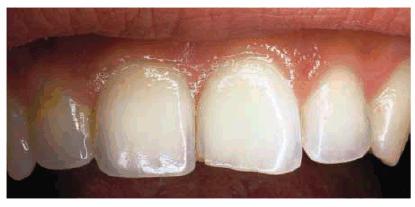

. Amount of tooth destruction present. Generally, small chips or

fractures are easily restored with direct bonded composite resin (Figur 323s1823d es 18-2A, and 18-2B). The esthetic result is excellent

and provides the patient with an economic, one-appointment solution without any

anesthesia.9,10 However, if the patient continues to chip or

Figur 323s1823d e 18-2A: This teenager chipped her maxillary front teeth.

Figur 323s1823d e 18-2B: The left central incisor was bonded with composite resin.